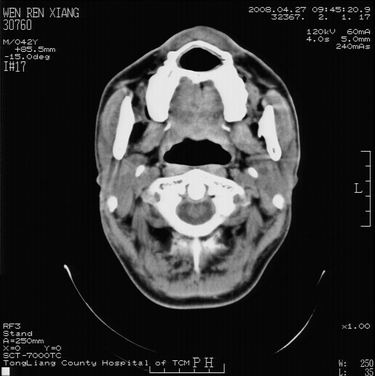

以下是引用随光逐影在2008-4-27 10:26:00的发言:[br]考虑为:上颌骨(中线区)含牙囊肿并向鼻腔穿破。

以下是引用前行在2008-4-27 11:30:00的发言:[br]含牙囊肿可能性大

以下是引用余辉在2008-4-27 16:43:00的发言:[br]考虑上颌骨正中囊肿,伴不全上颌骨正中裂,囊肿与鼻前庭有瘘道,所以表现为腔内炎性粘膜增厚而无囊液